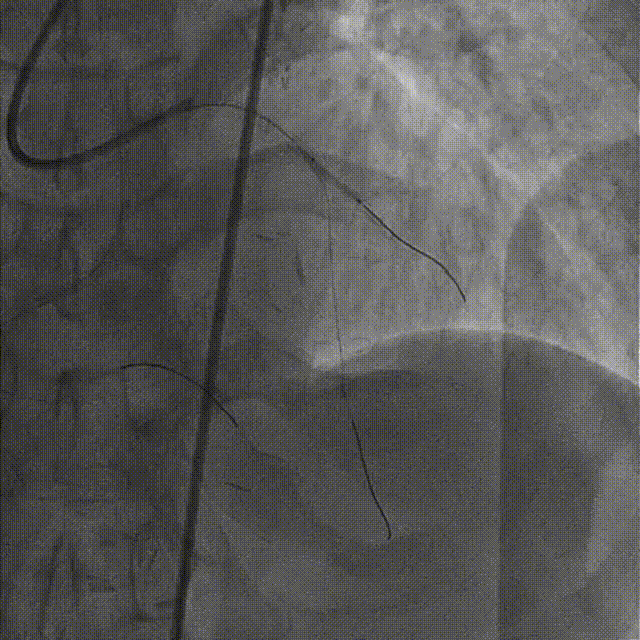

置7F UBS 3.75、6F JR 4.0指引导管至左右冠开口,分别送入Marvel导丝至LCX远段、RCA远端加强支撑,行双侧造影。

在微导管支撑下,Sion导丝无法经OM1心外膜侧枝逆向至LAD远段,改送Fielder XT-R导丝逆向至LAD远段。

HighTrack微导管跟进至闭塞病变远端,正向工作导丝做指引,应用Fielder XT-A导丝逆向通过闭塞段至LM内,反复尝试调整导丝未能进入正向指引导管。